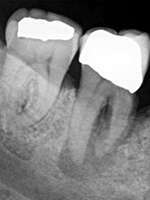

Carie, gingivite, abcès dentaire, sont les causes principales des douleurs buccales. Une douleur qui arrive le plus souvent, soudainement et de façon violente. Les maux de dent peuvent être extrêmement douloureux et lancinants, ils peuvent provoquer des maux de têtes, et sont capables de perturber la vie de tous les jours, mais également le sommeil.